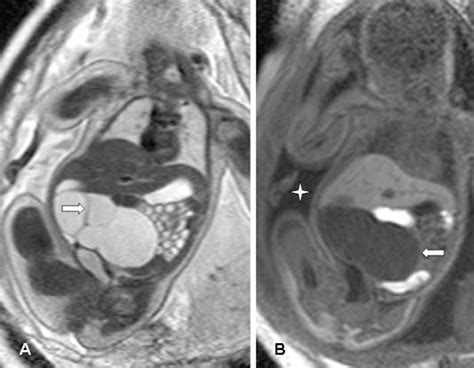

• Ultrasound: An imaging test that uses sound waves to create pictures of the internal structures, including the ovaries. Transvaginal ultrasounds are generally avoided during pregnancy, so transabdominal ultrasounds are typically used.